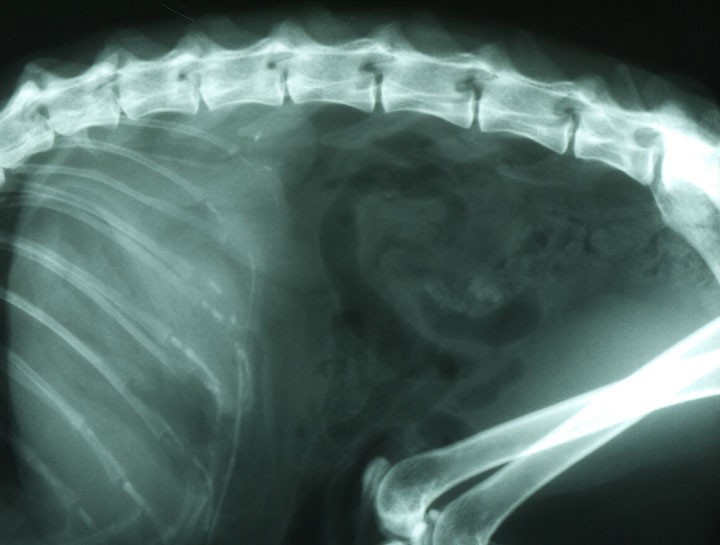

Digital x-rays assist in diagnosing illness & injury.

Digital radiology is the new conventional film x-ray. Digital x-rays allow us to better diagnose and treat sick and injured pets by providing us with high quality imaging results and reducing overall radiation exposure. They can capture digital images of both the body and teeth.